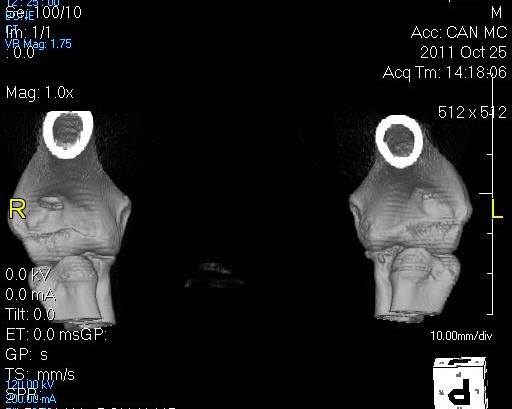

CT scan – Computed tomography (CT scan) may be necessary in some cases to make a diagnosis. A CT scan is a different type of x-ray and requires that your pet be anesthetized. The advantage of a CT scan is that it gives us a greater detailed image of the joint allowing us to detect mild changes. Sensitivity of a CT scan is >90% in diagnosing elbow dysplasia.

3-D image reconstruction of an elbow CT scan.